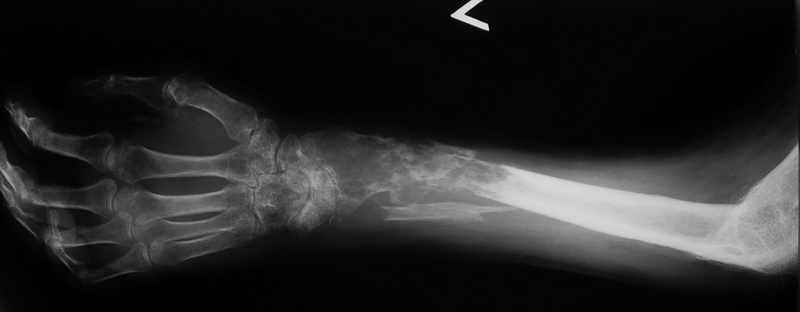

Всем привет!Кому интересно - может лицезреть мое личное наблюдение первичной костной лимфомы с поражением правой большеберцовой кости (см. аттач). Пациент: мужчина, 46 лет. Анамнез прослеживается в течение 1,5 лет - начало заболевания с появления болей.С уважением, Виталий Тазалов.

Ещё одно клиническое наблюдение - лимфома кости, до и после ПХТ и лучевой терапии.

Извините, но впечатление какое-то агрессивное! Вот Вам моя лимфома!

И продолжение - Вам под стать: а вот моя!